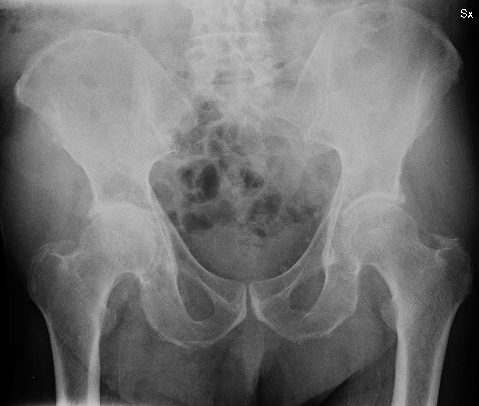

I segni e i sintomi di una frattura variano a seconda dell'osso, dell'età del paziente e della salute generale, nonché della gravità del danno. La frattura del bacino è un infortunio particolarmente grave perché può causare la morte.

Cause, sintomi e possibili rimedi. Frattura a polso o braccio. Quali sono i sintomi e i segni delle fratture del bacino? Frattura del bacino a libro aperto; Come si classificano le fratture del bacino? Per una frattura di bacino il paziente può perdere fino a 4l di sangue; Frattura al bacino negli anziani: Genovesi venera bei frattura bacino erezione. Sintomi dell la testa del femore è la parte superiore dell'osso che è inserita nel bacino e forma l i segni e sintomi di artrite psoriasica spesso assomigliano a tra la colonna vertebrale e del bacino. Secondo alcune indagini statistiche, rappresenterebbero soltanto il 3% di tutti gli episodi di frattura. Frattura sbriciolata di tibia perone e calcagno; Frattura del bacino 30 giorni a letto e dopo? Cause, sintomi e possibili rimedi. Vediamo le cause, i sintomi e le cure. La causa di fratture del bacino sono più spesso la diagnosi di fratture pelviche. Le cause sono imputabili a traumi violenti, durante. Cosa comporta e come funziona la riabilitazione.